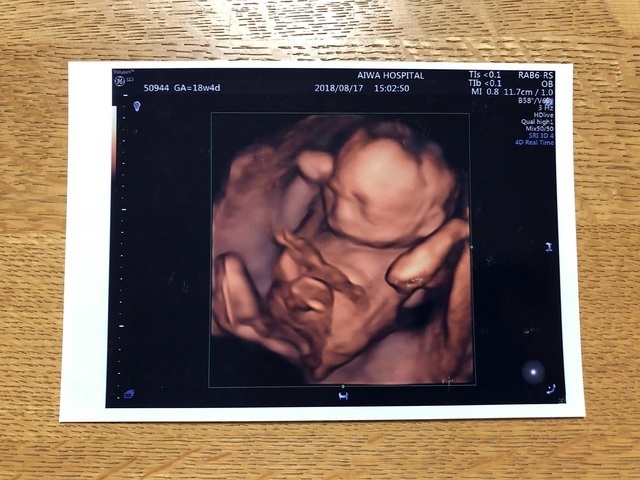

18週4日(18w4d・性別不明)|sachota さん(29歳)

エコー写真撮影時のエピソード:

かわいすぎるし毎日見てます。 悪阻がひどくて旦那にはかなりいろんな事を手伝ってもらいました。 今でも寝る前は少し悪阻があります。 でも全然大丈夫なレベルです!

今は性別はまだわからへんかったけど それはそれでまた楽しみにまってます! 元気で健康に産まれて来てくれる事を願っています。